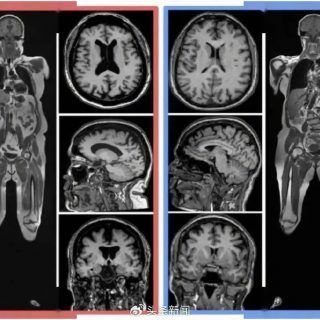

1 沙雕芝士 2024年1月11日 由 沙雕新闻 · Published 2024年1月11日 研究发现内脏脂肪越多大脑越小 近几年,越来越多的科学研究发现,大肚子的宰相能撑多大的船不知道,但很可能脑子不太好。23年8月,...